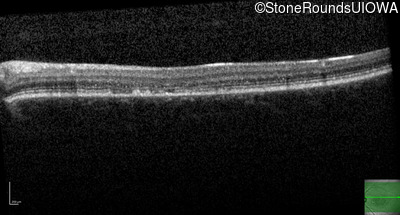

AR Stargardt Disease (IIA)

Age at visit: 22 years

This 22 year old woman first had difficulty seeing the blackboard at age 14 and this was not correctable with glasses.